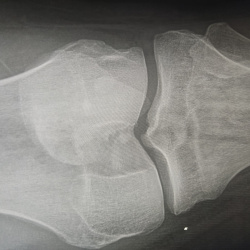

Здравствуйте, мужчина 35 лет, жалобы на боль, небольшую отёчность, временами повышения температуры. ДОА 1. Говорит раньше были травмы. Дефект по медиальной поверхности надколенника за счёт чего может...

21.06.2024 - 20:13